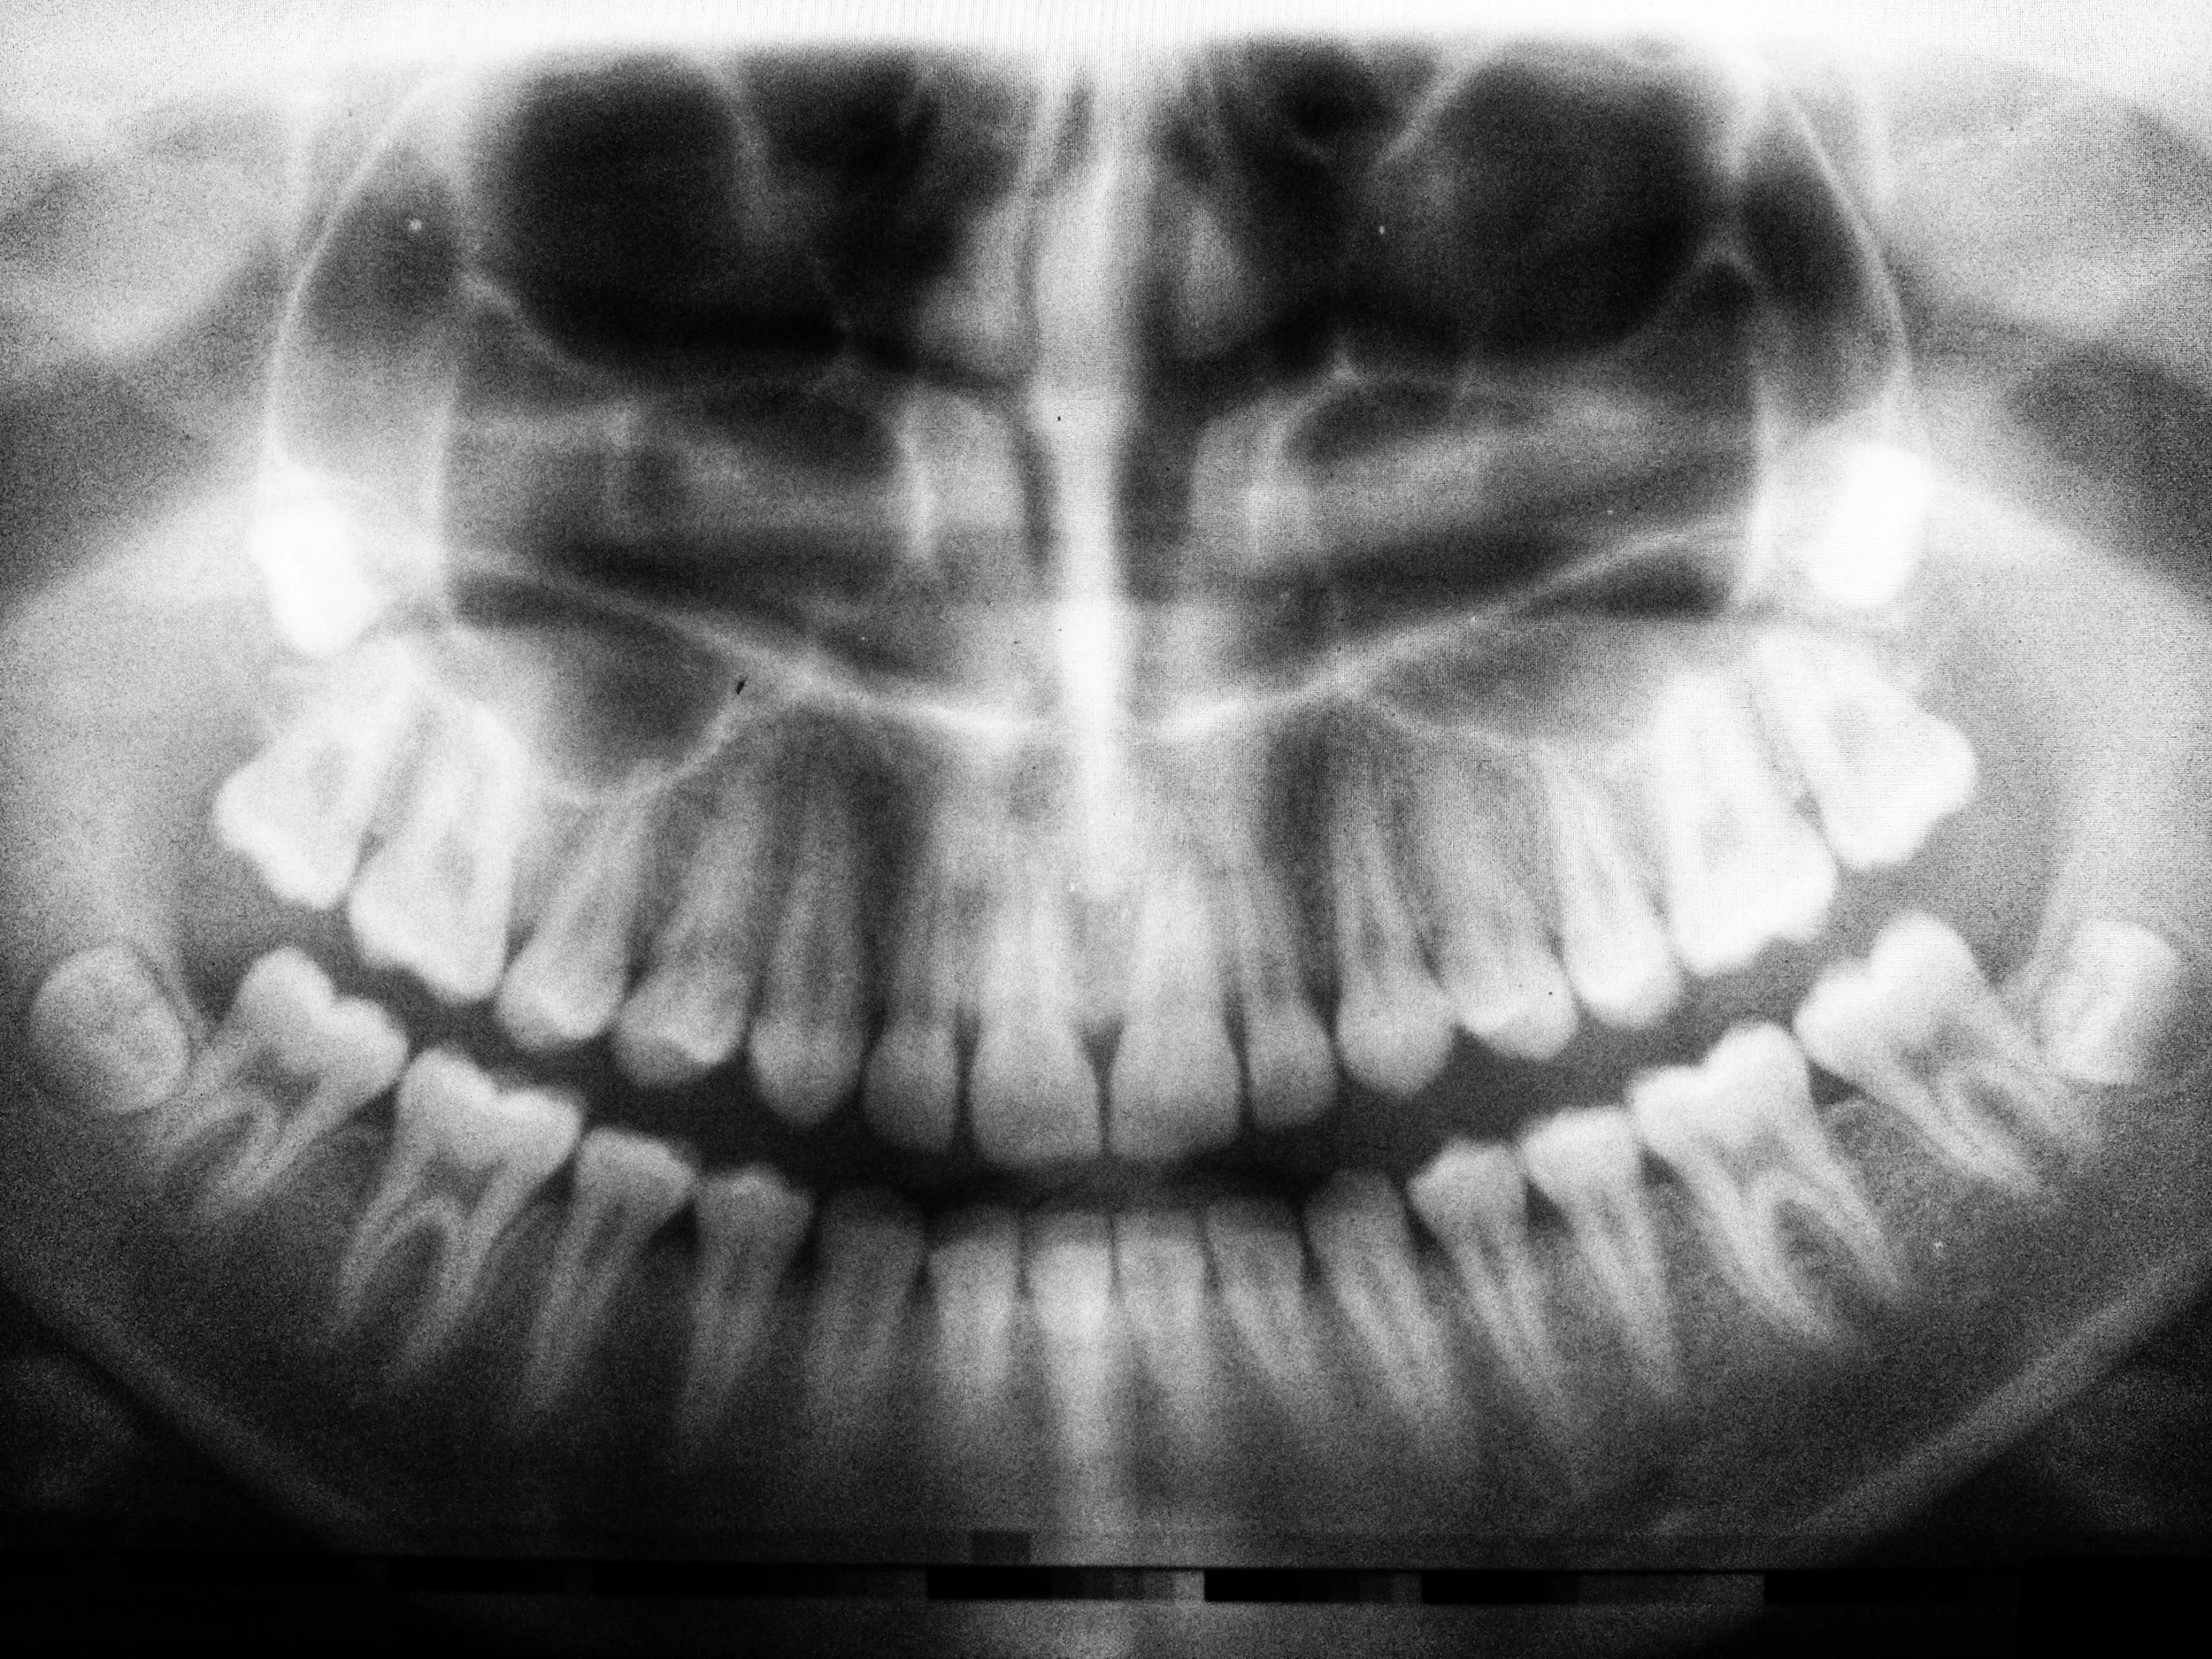

DENTAL X-RAYS

We have certified mobile dental x-ray equipment to be able to take and review the images in order to check the height of the bone, identify cavities or problems with restorations, as well as other concerns. Our mobile unit is digital, allowing us to take images using the least amount of radiation possible.